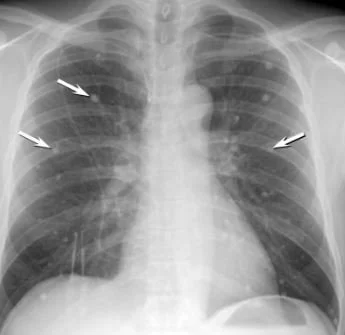

Histoplasma is a dimorphic fungus: In the soil it is filamentous, but in the body it transforms into a yeast form. These are then transported to regional nodes. A CXR of an individual with past  exposure which includes most of our patients CXR often shows calcified granulomas. Yeast forms can still be present in the granulomas.